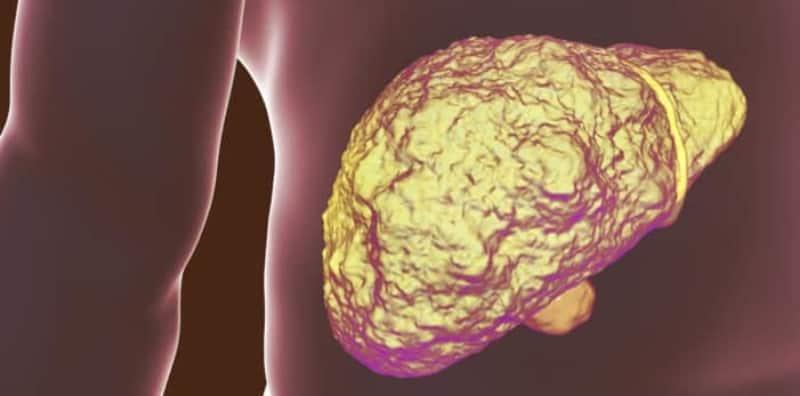

Apa itu penyakit sirosis hati alkoholik?

Sirosis hati alkoholik adalah parut pada hati disebabkan oleh tumbesaran tisu serat yang menggantikan sel hati yang rosak.

Sirosis hati tidak boleh sembuh walaupun selepas berhenti meminum alkohol.

Apakah punca sirosis hati alkoholik?

Kecederaan yang berulang dan berlebihan daripada penyalahgunaan alkohol menyebabkan sirosis hati alkoholik.

Apabila tisu hati mula untuk menjadi parut, hati tidak dapat berfungsi dengan baik seperti biasa.

Hasilnya, badan tidak dapat menghasilkan protein yang cukup atau menapis toksin keluar daripada darah seperti yang sepatutnya.

Penyakit sirosis hati boleh berlaku disebabkan oleh pelbagai punca.

Walau bagaimanapun sirosis hati alkoholik berkait secara langsung dengan pengambilan alkohol.